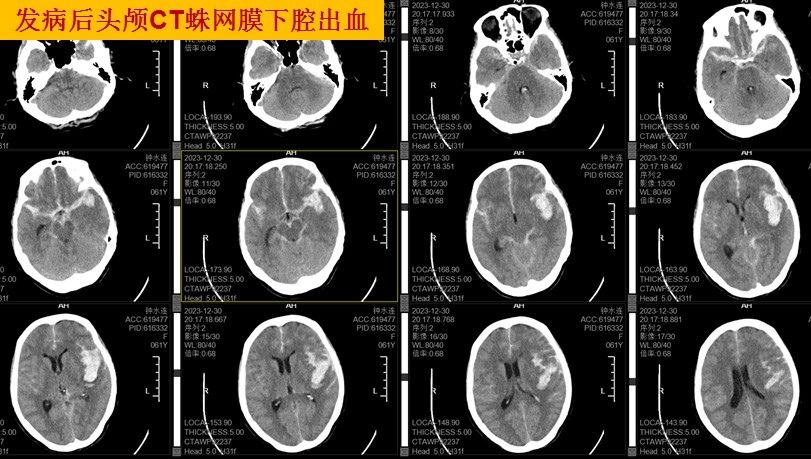

近期,患者钟阿姨(61岁)像平时一样日常生活中,突然,毫无征兆的感觉头痛异常厉害,像“快要爆炸”一样,很快就出现意识不清,昏迷不醒,家人发现后立刻拨打了120将钟阿姨送来佛冈县人民医院,完善了头颅CT检查,一看吓一跳,原来是蛛网膜下腔出血、脑内出血!

此患者自发性蛛网膜下腔出血、脑内出血最大可能的原因就是颅内的血管病变--颅内动脉瘤破裂,须立刻完善脑血管造影检查(DSA)进一步查明出血原因,取得钟阿姨家属同意后,便开通绿色手术通道进行介入手术。